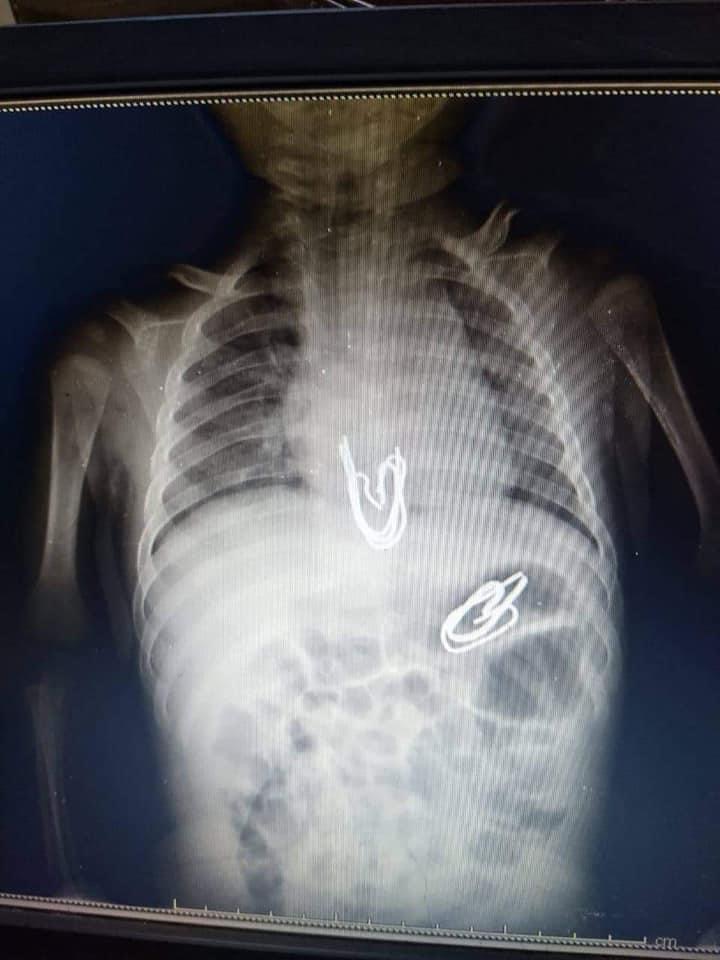

وقال لـ لقاهرة 24: نجح الفريق الطبي بمستشفى الأطفال بجامعة المنصورة، في إجراء عملية جراحية غاية في الدقة لرضيع عمره لا يتجاوز 3 أشهر، حيث قام ببلع 5 مشابك معدنية يتراوح طول الواحد 3 سنتيمترات بإجمالي مساحة 15 سنتيمترات تقريبًا.

وتابع: تم إجراء أشعة على البطن، وتبين وجود مجموعة من الدبابيس في المريء، وأخرى في المعدة، ولأن هذه المشابك ذات أطراف حادة فكان هناك تخوف من أن تكون جرحت جدار المعدة والمريء، فتم عمل أشعة مقطعية أثبتت عدم وجود جروح وتم إجراء العملية واستخراج 5 مشابك معدنية.